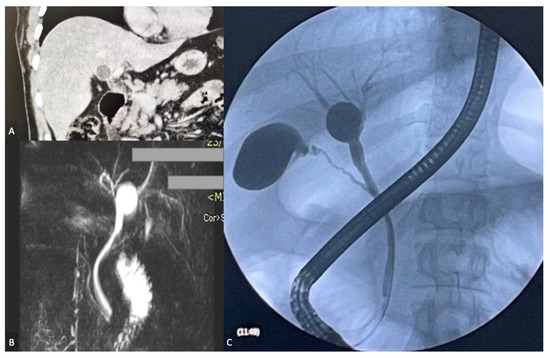

2. Case Report